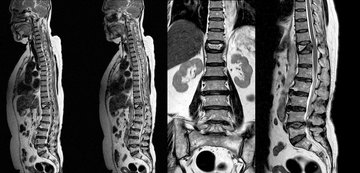

• Wirbelsäuleninfiltrationen